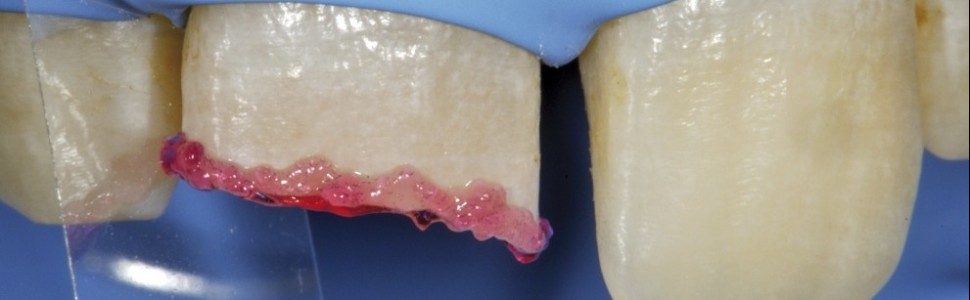

Odbudowa zębów przednich techniką dwuwarstwową

Obecnie jest dostępna prostsza metoda, opierająca się na wykorzystaniu materiału pozwalającego na pracę techniką dwuwarstwową (zębina i szkliwo). Taką właśnie technikę zastosowano w opisanym przypadku młodego pacjenta.